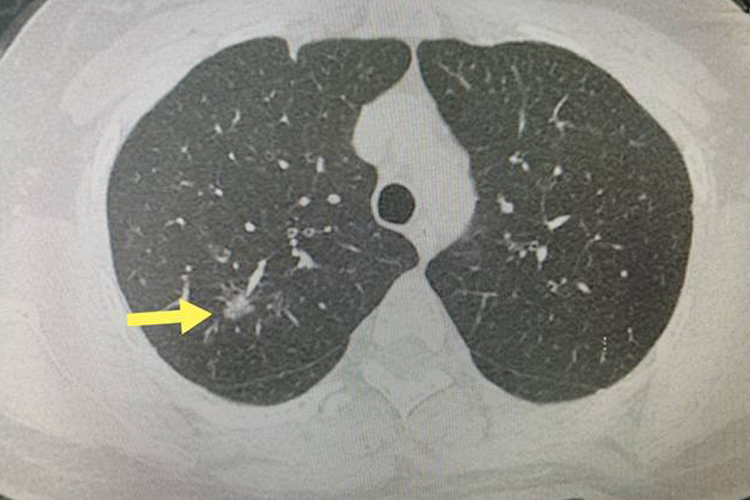

肺磨玻璃影是肺部CT检查中的常见表现,可能由肺炎、肺泡炎、肺结核、肺纤维瘤及肺癌等多种原因引起,如果出现肺磨玻璃影,建议及时到医院配合医生进行治疗,以免耽误病情。

5、肺癌:恶性肿瘤在肺部生长时,也可能表现为磨玻璃影,病情最为严重,建议及时就医明确病因并采取药物、手术等综合治疗措施。